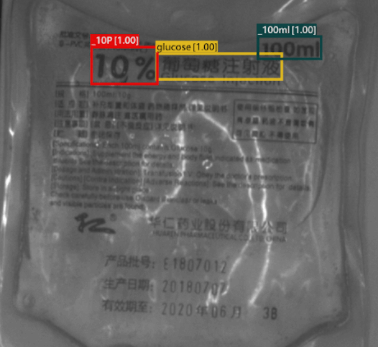

Classification

Dextrose Solution